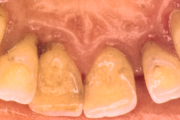

- igemed veritsevad (19)

- igemed punetavad (21)

- igemed on tursunud/vohavad (17)

- puudulik suuhügieen (5)

- igemepealne hambakivi (5)

- hammaste tundlikkus (9)